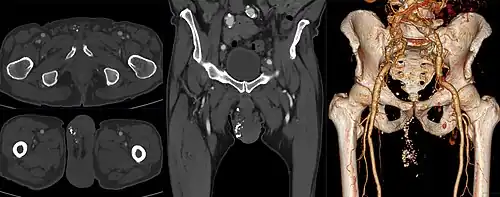

Phleboliths (seen as punctiform calcifications) in the scrotum of an individual with varicocoele.

A phlebolith is a small local, usually rounded, calcification within a vein. These are very common in the veins of the lower part of the pelvis, and they are generally of no clinical importance. When located in the pelvis they are sometimes difficult to differentiate from kidney stones in the ureters on X-ray.[1]